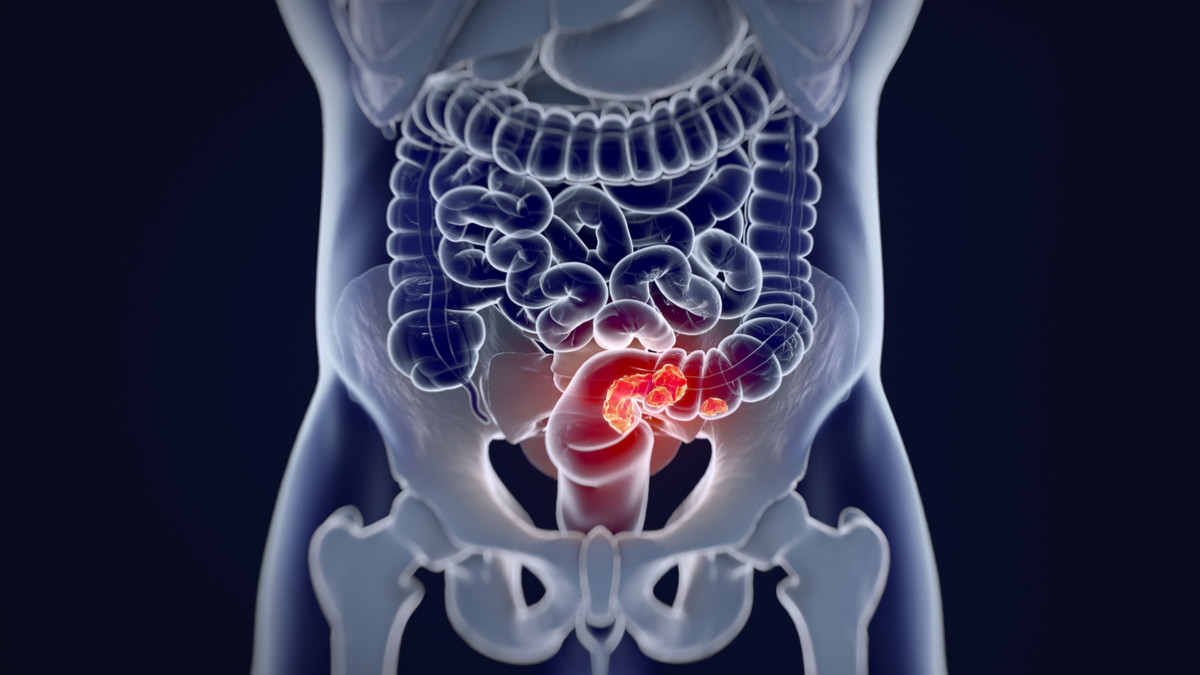

INews Payakumbuh – Kanker Usus Intai atau yang sering disebut juga sebagai kanker kolorektal, adalah salah satu jenis

Data menunjukkan, angka kasus kanker usus pada orang yang lebih muda, khususnya mereka yang berusia di bawah 50 tahun, semakin meningkat dalam beberapa tahun terakhir. Hal ini menjadi perhatian serius, karena gaya hidup dan pola makan yang tidak sehat menjadi salah satu faktor utama yang berkontribusi pada peningkatan risiko kanker usus pada generasi muda.

Kanker Usus Intai Menurut para ahli, beberapa jenis makanan dan minuman tertentu dapat meningkatkan kemungkinan seseorang mengembangkan kanker usus. Makanan dan minuman yang kaya lemak jenuh, gula berlebih, serta proses pengolahan yang tidak sehat bisa merusak fungsi pencernaan dan meningkatkan peradangan dalam tubuh, yang pada akhirnya memicu pertumbuhan sel kanker.